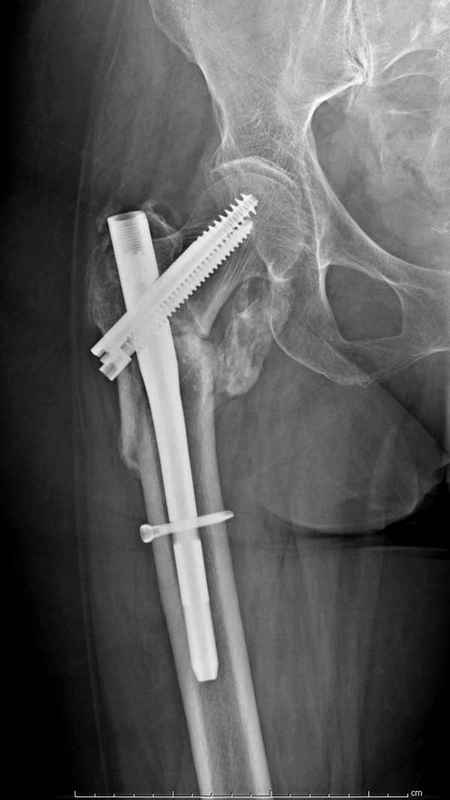

Здесь 83 года, травма в результате падения